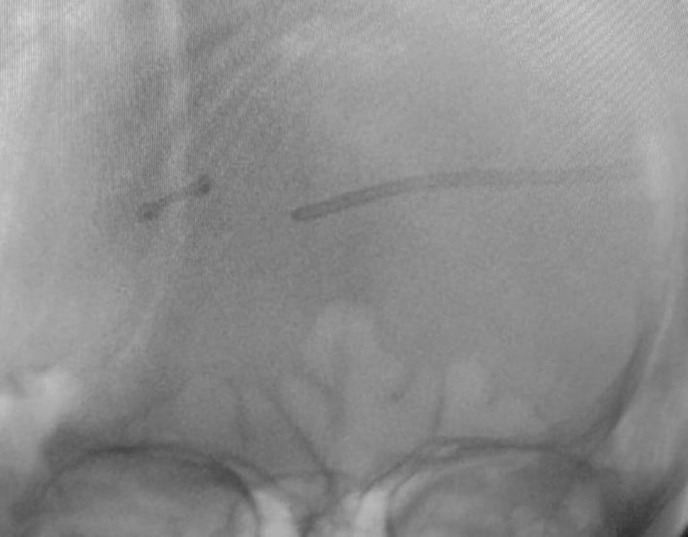

Background: Ventricular catheter (VC) misplacement is one of the most common causes of ventriculoperitoneal (VP) shunt malfunction and revision surgery. Most of the VC placements are done by freehand method. We evaluated the use of intraoperative fluoroscopy for assessing VC placement.

Materials and methods: A total of 70 patients were enrolled in the study. Patients with hydrocephalus who required cerebrospinal fluid diversion were enrolled in the study. Thirty-five patients were placed in the control group (patients in whom intraoperative fluoroscopy was not done), and 35 patients were placed in the test group (patients in whom intraoperative fluoroscopy was done). Patients with trapped ventricles and multiloculated hydrocephalus were excluded from the study. VP shunt insertion was done through standard Keen's point.

Results: The positioning of VC was optimal in 40 patients, with a significant difference between the test group and the control group. Gross malpositioning was seen in seven patients: four in the test group and three in the control group. All gross malpositioned VCs in the test group were corrected intraoperatively. VC crossing midline was less in the test group as compared to the control group.

Conclusion: Fluoroscopy is an easy and cheap method to assess VC position intraoperatively. It is readily available and helps us in avoiding resurgery due to VC misplacement and subsequent blockage.